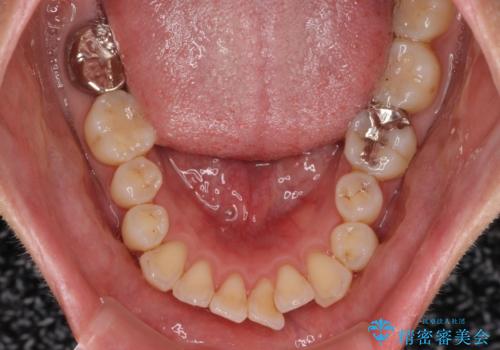

- 上下の出っ歯を気にして来院された患者様です。

口元を積極的に引っ込めるために、上下左右の第一小臼歯を4本抜歯することとしました。

また、上下前歯は舌の突出癖による開咬となっていたため、舌のトレーニングを徹底するよう指示しました。